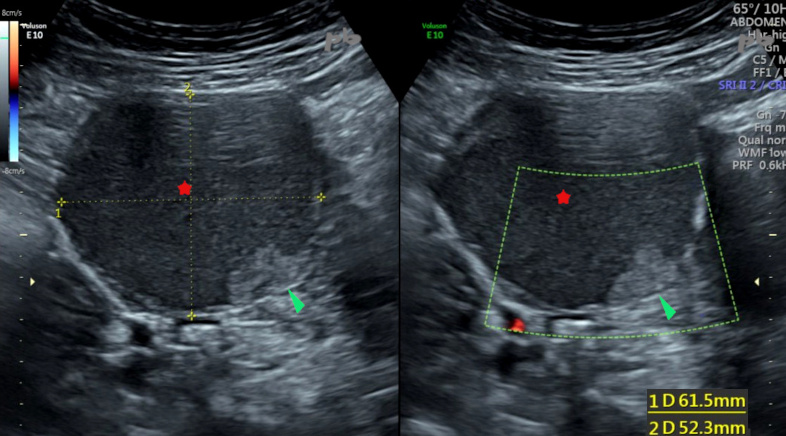

Echo et doppler couleur

Kyste endométriosique ovarien droit à contenu hypoéchogène, finement particulaire (★). Présence de quelques images végétantes endokystiques non vascularisées (►).

Localisations d’endométriose profonde par ailleurs (non montrées).